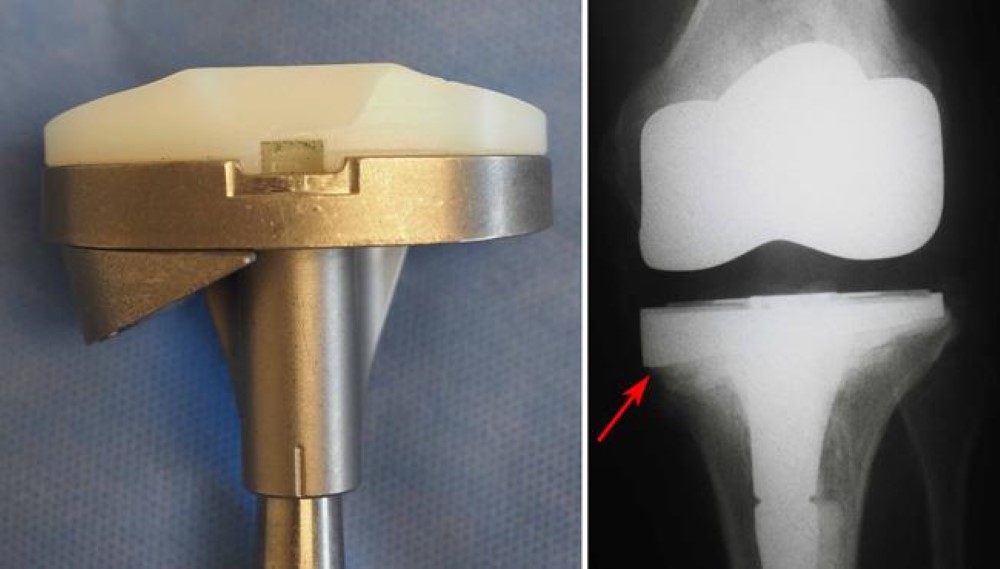

Damage to the bone may make it difficult for the doctor to use standard total knee implants for revision knee replacement. In most cases, he or she will use specialized implants with longer, thicker stems that fit deeper inside the bone for extra support.

In this implant the femoral component is made of stainless steel and the tibial tray and the insert are together made of polyethylene. The advantage it has is that more poly is available and hence it lasts longer, also cost-wise it is cheaper than the other implants.